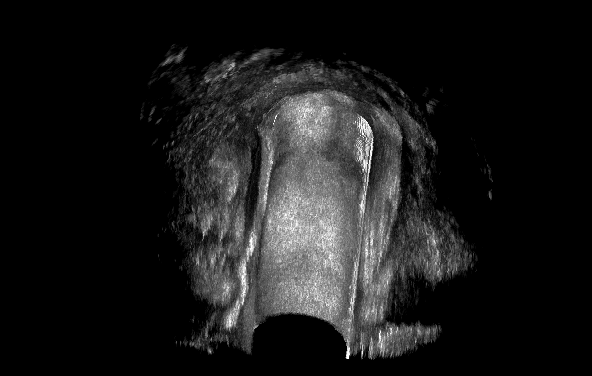

针对上述情况,肛瘘过氧化氢超声造影诊断技术(HPUS)应需而生,它是经由肛瘘外口处注入过氧化氢溶液,这样可以显著增强瘘管的回声效果,使之由低回声变为强回声,从而达到明确诊断的目的。

瘘道与周围组织回声存在明显的差异,大多数情况下瘘道主支、分支的识别是比较容易的,但在反复发作或术后复发的病例中可能存在辨别困难,其主要原因是瘢痕与瘘道相近的低回声造成了鉴别困难。其次,瘢痕后方宽大的声影影响了其深方组织的扫查。过氧化氢超声诊断技术应用后,经肛瘘外口注入的过氧化氢迅速形成无数微气泡,瘘道内出现强回声气体线条,与周围组织回声形成鲜明对比,瘘道路径被勾勒出来,可以增强瘘道的显示程度,检查出常规腔内超声可能遗漏的病变,为临床制定手术方案提供准确的影像依据,彻底清除感染,避免术后复发。